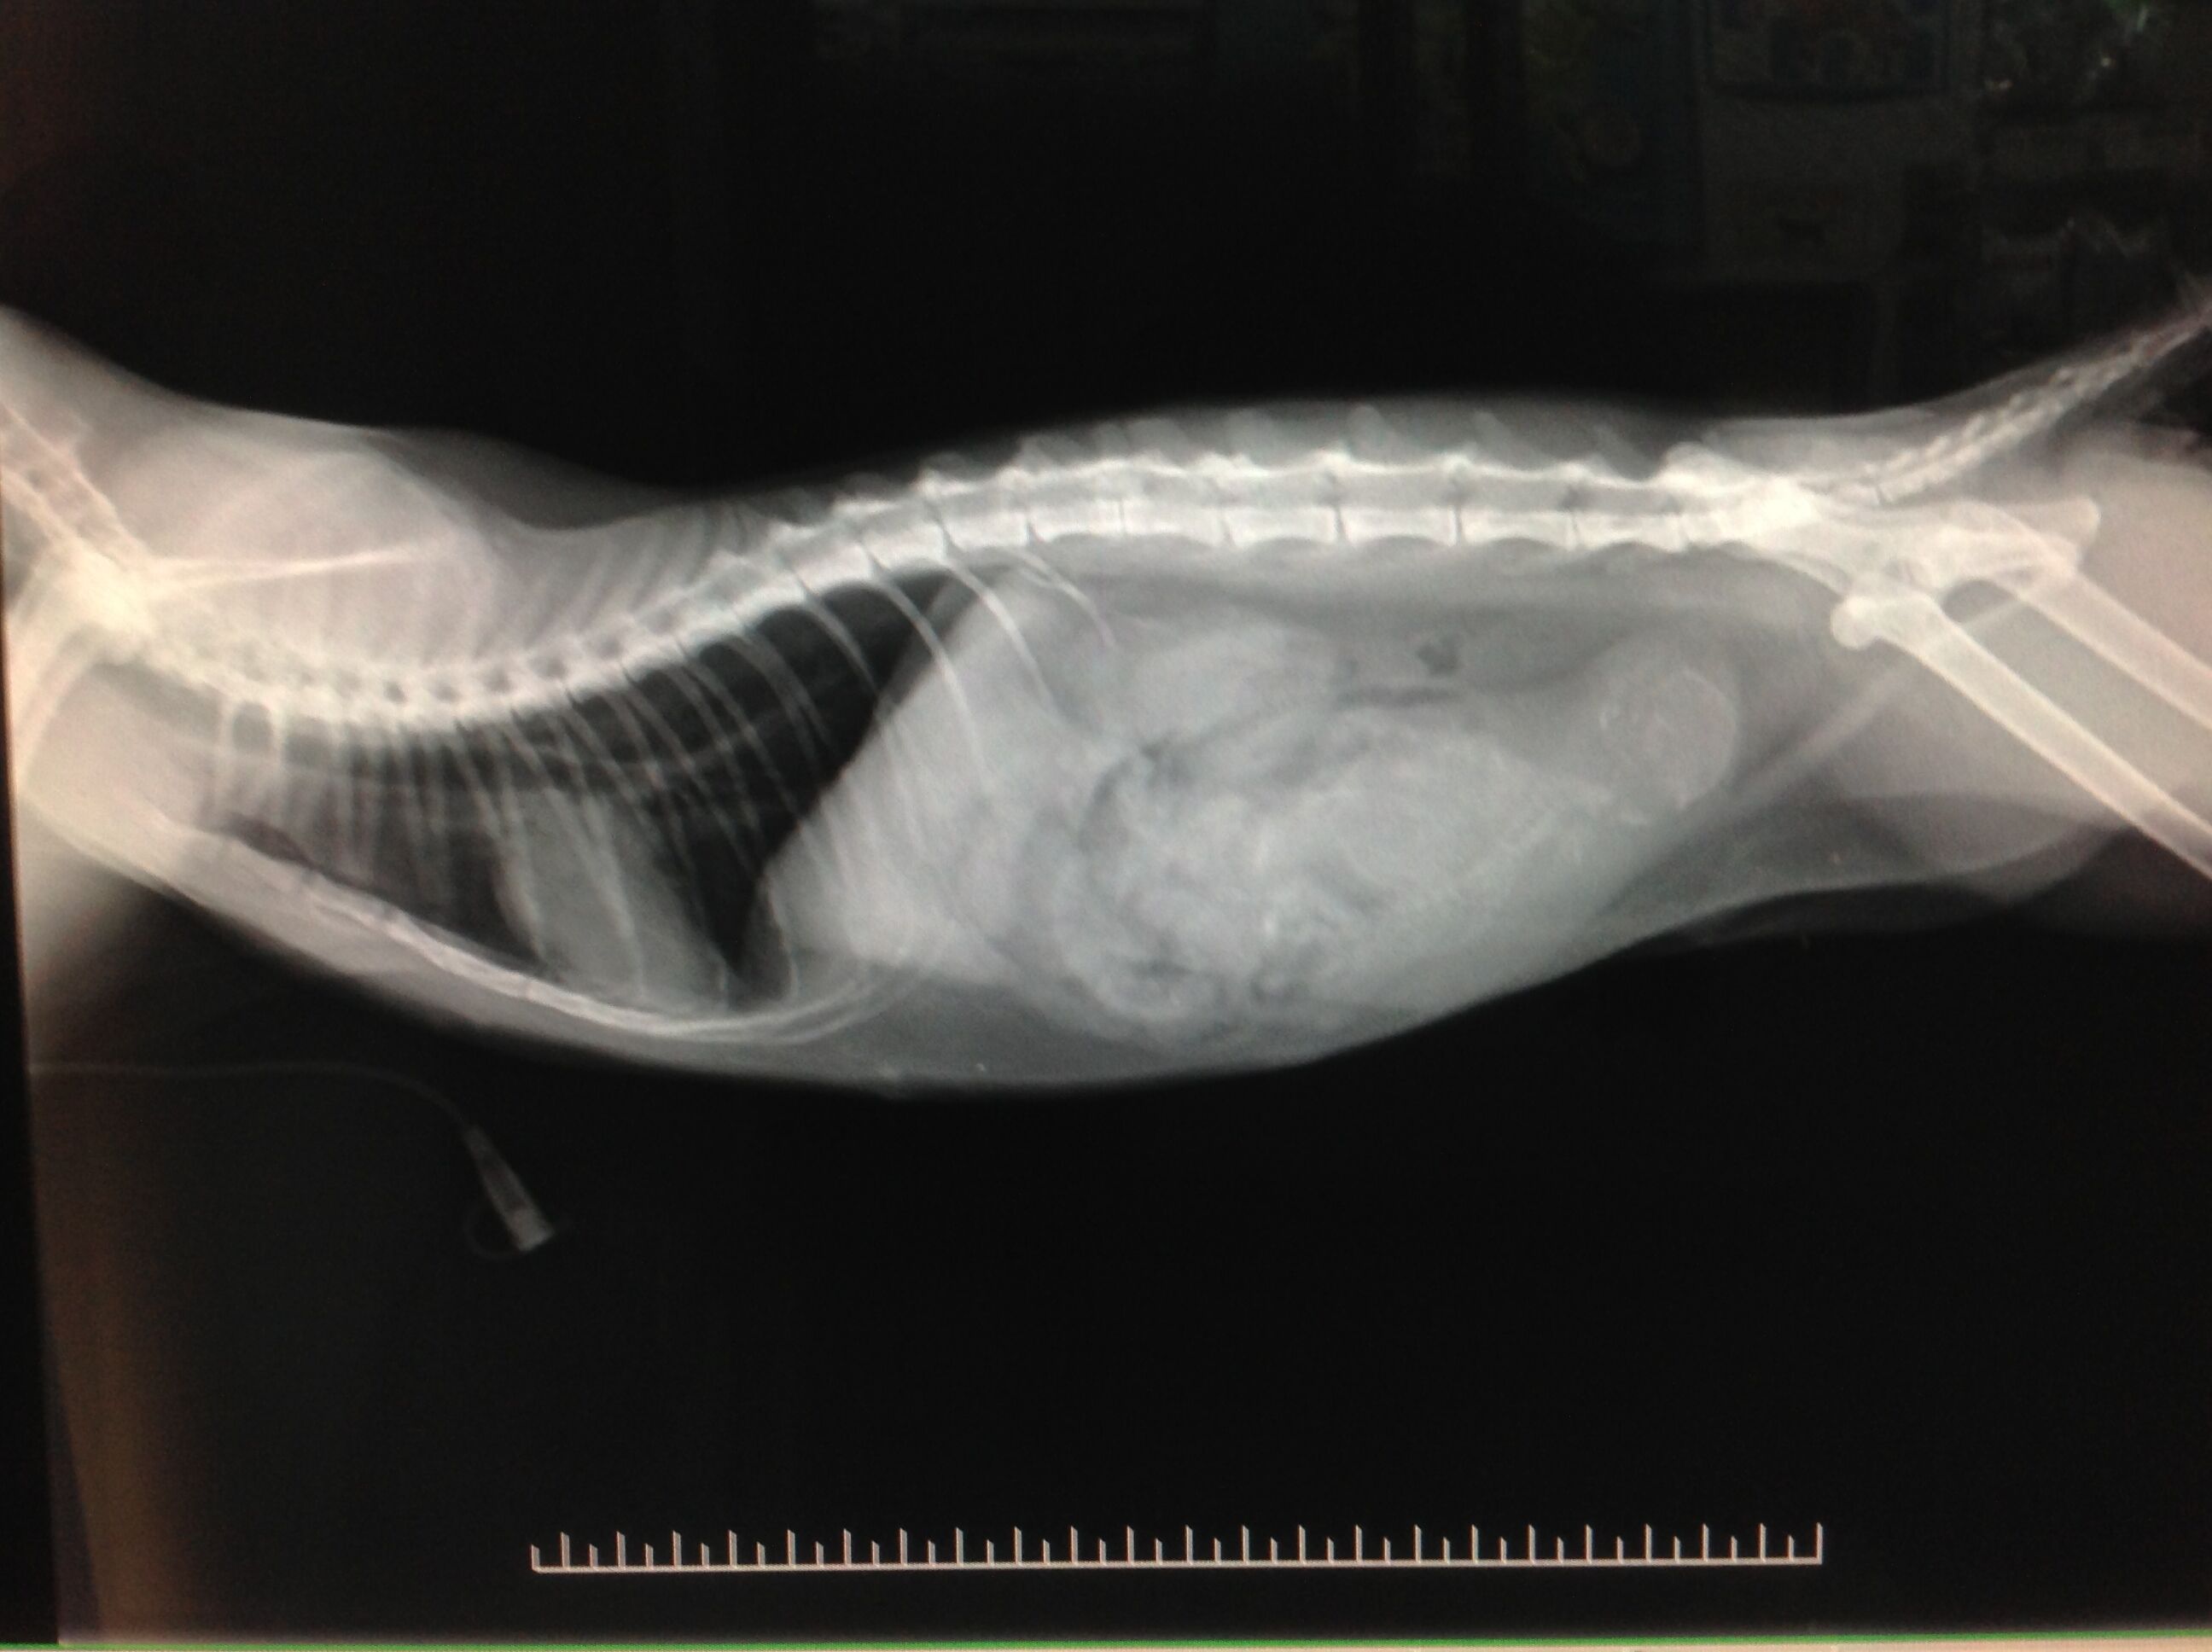

檢查發現貓咪有嚴重內出血的情形,X光片顯示貓咪懷孕了,小貓約50多天大。